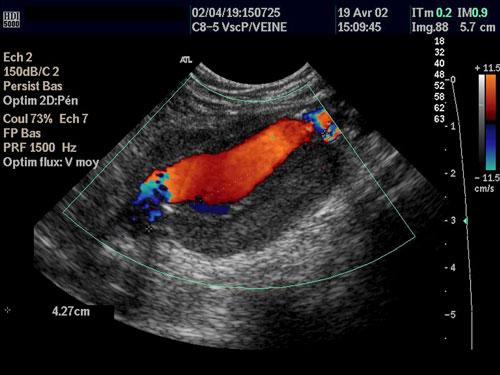

美国西雅图市华盛顿大学的劳伦斯·克鲁姆(lawrence crum)称,一种超高强度的超声波可以烧灼出血的动脉血管。他所在的超声波科技公司研制出一种手持式设备,可使外科医师对人体内部富含血液的器官进行切割手术,在切割之后立即对血管进行烧灼愈合,这样的手术方法无需在人体皮肤上切割伤口。目前,无创口手术治疗已在动物实验中取得了成功,预计今年将进入人体临床实验。